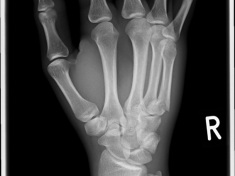

Röntgenbilder